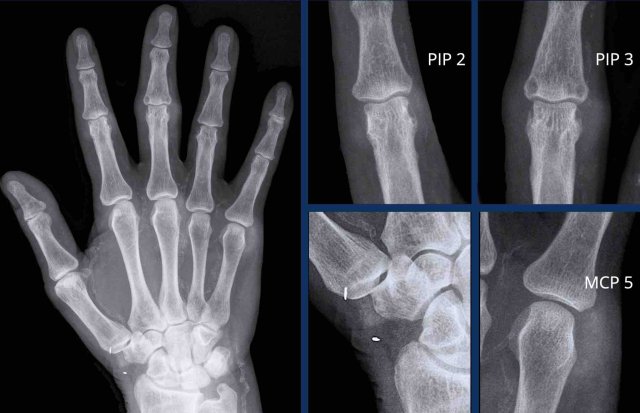

When in doubt, think gout

This is a difficult case.

Small bilateral erosions of the PIP joints on both sides are seen.

The arrowheads show that the erosions are more juxtaarticular in this patient that proved to have gout.

Based on the distribution, rheumatoid arthritis and psoriatic arthritis would have been an option.

However then the erosions would have been more marginally located.

Also, the MCPs are spared, making the diagnosis of rheumatoid arthritis less likely.

Soft tissue swelling

This case is also challenging.

Multipele joint are affected, but there is no typical distribution.

The only thing that these joints have in common is the surrounding hyperdense soft tissue swelling.

This was due to gout tophi.